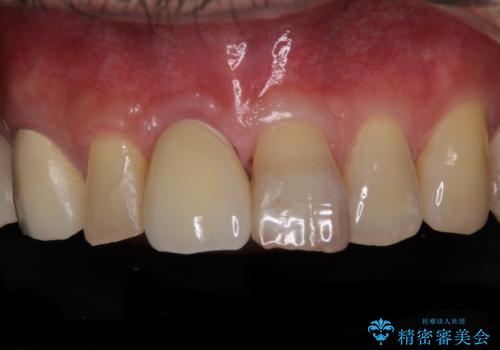

咬み合わせが非常に強く、臼歯のみに咬合力が集中している咬み合わせだったので、根管治療後はPGAクラウン(白金加金合金クラウン)にて補綴する治療計画となりました。

PGAクラウンにしたことで咬み心地に全く違和感がなく、気にされていた審美面も、奥歯でありそれほど目立たないこともありますが、白金加金の色を気に入っていただけたので、患者様には大変満足していただけました。